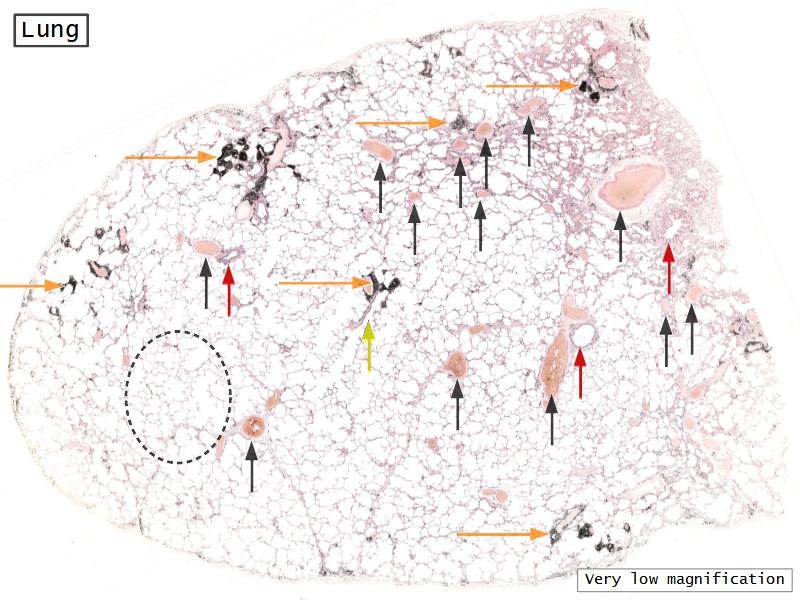

Slides: Respiratory System

- Slide 72 & 74: Lung

Bronchi - Transitions

- Intrapulmonary bronchi

- Irregular cartilage

- Respiratory epithelium

- Glands

- Bronchioles

- Smooth muscle REPLACE cartilage

- Ciliated columnar > Ciliated cuboidal

- NO glands - goblet cells -> secretory cells

- Terminal bronchioles

- Smooth muscle

- Ciliated cuboidal epithelium

- Secretory cells

- Respiratory bronchioles

- Conducting -> Respiratory

- Simple cuboidal epithelium

- Secretory cells

- Alveoli

Lungs